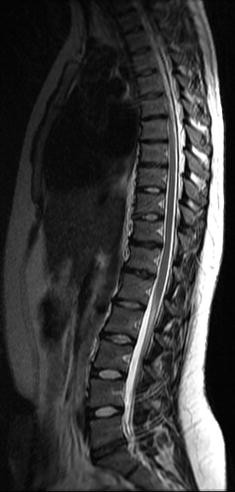

The thoracic spine has 12 vertebrae, T1 through T12, each of which is separated by a disc These vertebrae are attached to the ribs T1 and T12, at the top and bottom, are also connected to the cervical and lumbar spine, respectively It's important to understand the physiological structure because the thoracic portion of the spine plays a very strong protectiveIf the discs become displaced, or herniated, they can impinge on surrounding structures and cause uncomfortable symptoms The most commonly involved discs are the ones located between the T9 and T10 vertebrae, the T10 and T11 vertebrae, and the T11 and T12 vertebrae Pain Pain is one of the primary symptoms of degenerative thoracic spine disease The pain is usually located in the T12 spinal cord injuries will affect sensation and mobility in the lower half of the body Below, we'll discuss 5 possible complications that can occur in individuals with T12 SCIs 1 Bladder and Bowel Dysfunction Inability to control the bowel and bladder muscles or inability to feel when they are full can cause leakage that you cannot feel or be aware of Catheterization, bladder

Each rubbery intervertebral disk provides a slightly flexible connection between the vertebral bodies and acts as a shock absorber to prevent collisions between the vertebrae The vertebral arch of T12 is thicker and stronger than its counterparts in the other thoracic vertebrae and in many ways resembles the vertebral arches of the lumbar vertebrae A pair of strongIntervertebral disc degeneration primarily causes thoracic discogenic pain syndrome Thoracic disc lesions are primarily degenerative of nature and affect mostly the lower part of the thoracic spine Three quarters of incidence occurs below T8, with T11T12 being most common The exact cause of disc degeneration is believed to be multifactorialAt T1112 there is a moderate posterior disc herniation which begins in the left paracentral position, but extruded disc material is seen extending caudally behind the T12 vertebra and extending down the midline This does result in mild spinal cord impingement Mild diffuse annular disc bulge is seen at T12L1 without nerve root encroachment

A recent MRI has found I have multilevel degenerative disc disease, L5S1 facet arthropathy, mild right paracentral disc extrusion at T4T5 and multilevel disc bulge (T7T8,T6T7,T8T9, T11T12) would read more Affected levels were as follows 2 patients with disc herniation at T10–T11 disc, 4 patients at T11–T12, 3 patients at T12–L1, 6 patients at L1–L2, and 11 patients at L2–L3 The level of disc space of interest was confirmed with wholespine plain roentgenograms The caudal end of the cord was judged by magnetic resonance imaging and computed tomographic myelogramSpine degeneration is common in T11 and T12 T12 is where the thoracic and lumbar spine meet This link is subject to forces from daily activity, such as bending and twisting, which lead to degeneration Not surprisingly, most thoracic disc herniations occur in this area Less commonly, a thoracic disc may herniate suddenly (an acute injury)

The Lumbar Spine was normal but they managed to get a partial view of t11t12 and they suspected that it was abnormal I was sent for an MRI of my Thoracic Spine and that revealed that I had a herniated disc at t11t12 Last week I was sent to UCSF Spine Center for a consultation on my back and the doctor there said that I have a large herniation and that the type of injuryAmong thoracolumbar junction disc herniations, T10T11 and T11T12 disc herniations were considered upper neuron disorders, T12L1 disc herniations were considered lower neuron disorders, L1L2 disc herniations were considered mild disorders of the cauda equina and radiculopathy, and L2L3 disc hern The T11–T12 disc is the most vulnerable because of greater mobility and posterior longitudinal ligament weakness at this level Only 4% of TDHs are located above T3–T4 Cases of TDH complicating proximal junctional syndrome after thoracolumbar fusion have been reported